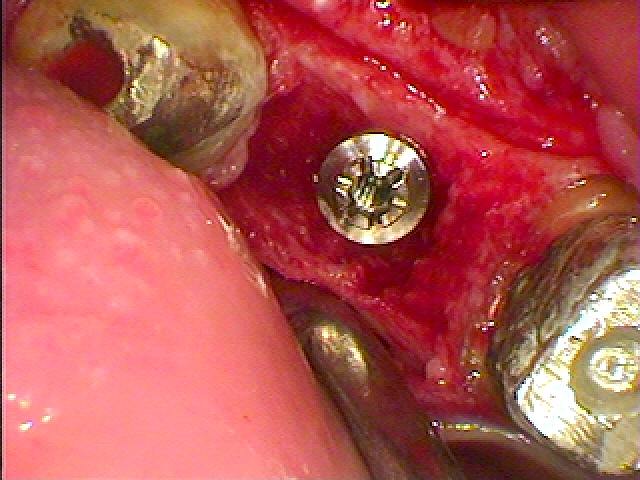

インプラント埋入になります

骨欠損が大きくGBRしていきます